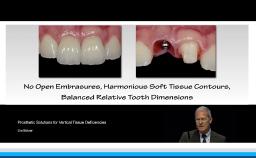

This lecture explains the trends in implant dentistry in a digital world: using digital impressions to obtain milled, printed, or digital casts; designing virtual prostheses via digital diagnostic wax-ups; and incorporating the patient’s cone beam CT into a digital workflow. This practice philosophy embraces prosthodontic-driven treatment planning in completely and partially edentulous arches through identifying the ideal prosthesis and creating prefabricated components. This presentation further demonstrates how this philosophy can lead to uneventful treatment that minimizes complications. The speaker emphasizes the key relationships between teeth, lips, and the residual ridge that indicate the optimal three-dimensional position for implant prostheses, and he advocates for the use of interim prostheses.